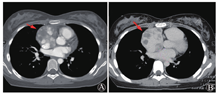

患者行TEE提示右心房及心包内可见多处中低回声团块影,最大位于近右房室沟,大小约49 mm×25 mm,其内血流丰富,并再次观察TTE,在非标准切面显示右房占位(图2)。考虑肿瘤性病变可能性大。胸部增强CT见右心部分心包增厚,右心房、房间隔多发富血供占位,部分明显强化,部分成分强化不明显,不除外血栓形成(图3)。PET/CT躯干断层显像:右心房增大,形态欠规则,密度不均匀,右心房、右心室及相邻心包脂肪间隙代谢不均匀异常增高,SUVmax 11.9,不除外恶性病变可能;T2椎体左后方肌间隙代谢增高灶,SUVmax 5.3,性质待定。颈胸椎旁肌肉MR增强及DWI成像均未见异常。

A:右心房形态不规则,可见多发软组织密度占位(箭头所示);B:右房、房间隔多发占位,部分明显强化,部分强化不明显(箭头所示),不除外血栓